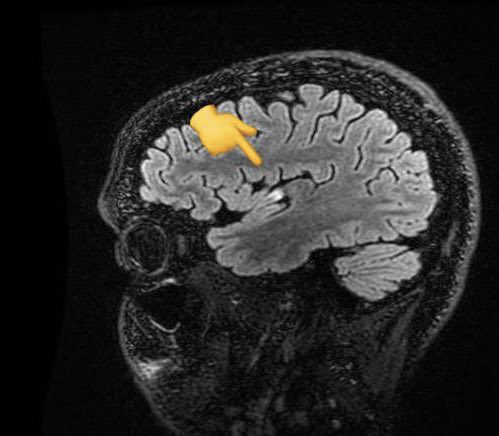

Família com quatro irmãos médicos cardiologistas. Um deles jovem, atleta, toma a vacina da AstraZeneca.15 dias depois tem um AVC isquêmico (causado por coágulo em uma artéria no cérebro).👇

Os médicos acharam uma característica no coração do paciente chamada Forame Oval Patente que *às vezes* (não em todos que têm) pode ter relação com formação de coágulos no coração que podem migrar para o cérebro, causando um AVC.

Como o paciente não tinha nenhum problema que pudesse gerar distúrbios de coagulação, suspeitaram que o FOP poderia ter favorecido a ocorrência do AVC.

Outros personagens do fio: Tomografia mostra avc no cérebro.Ecocardiograma